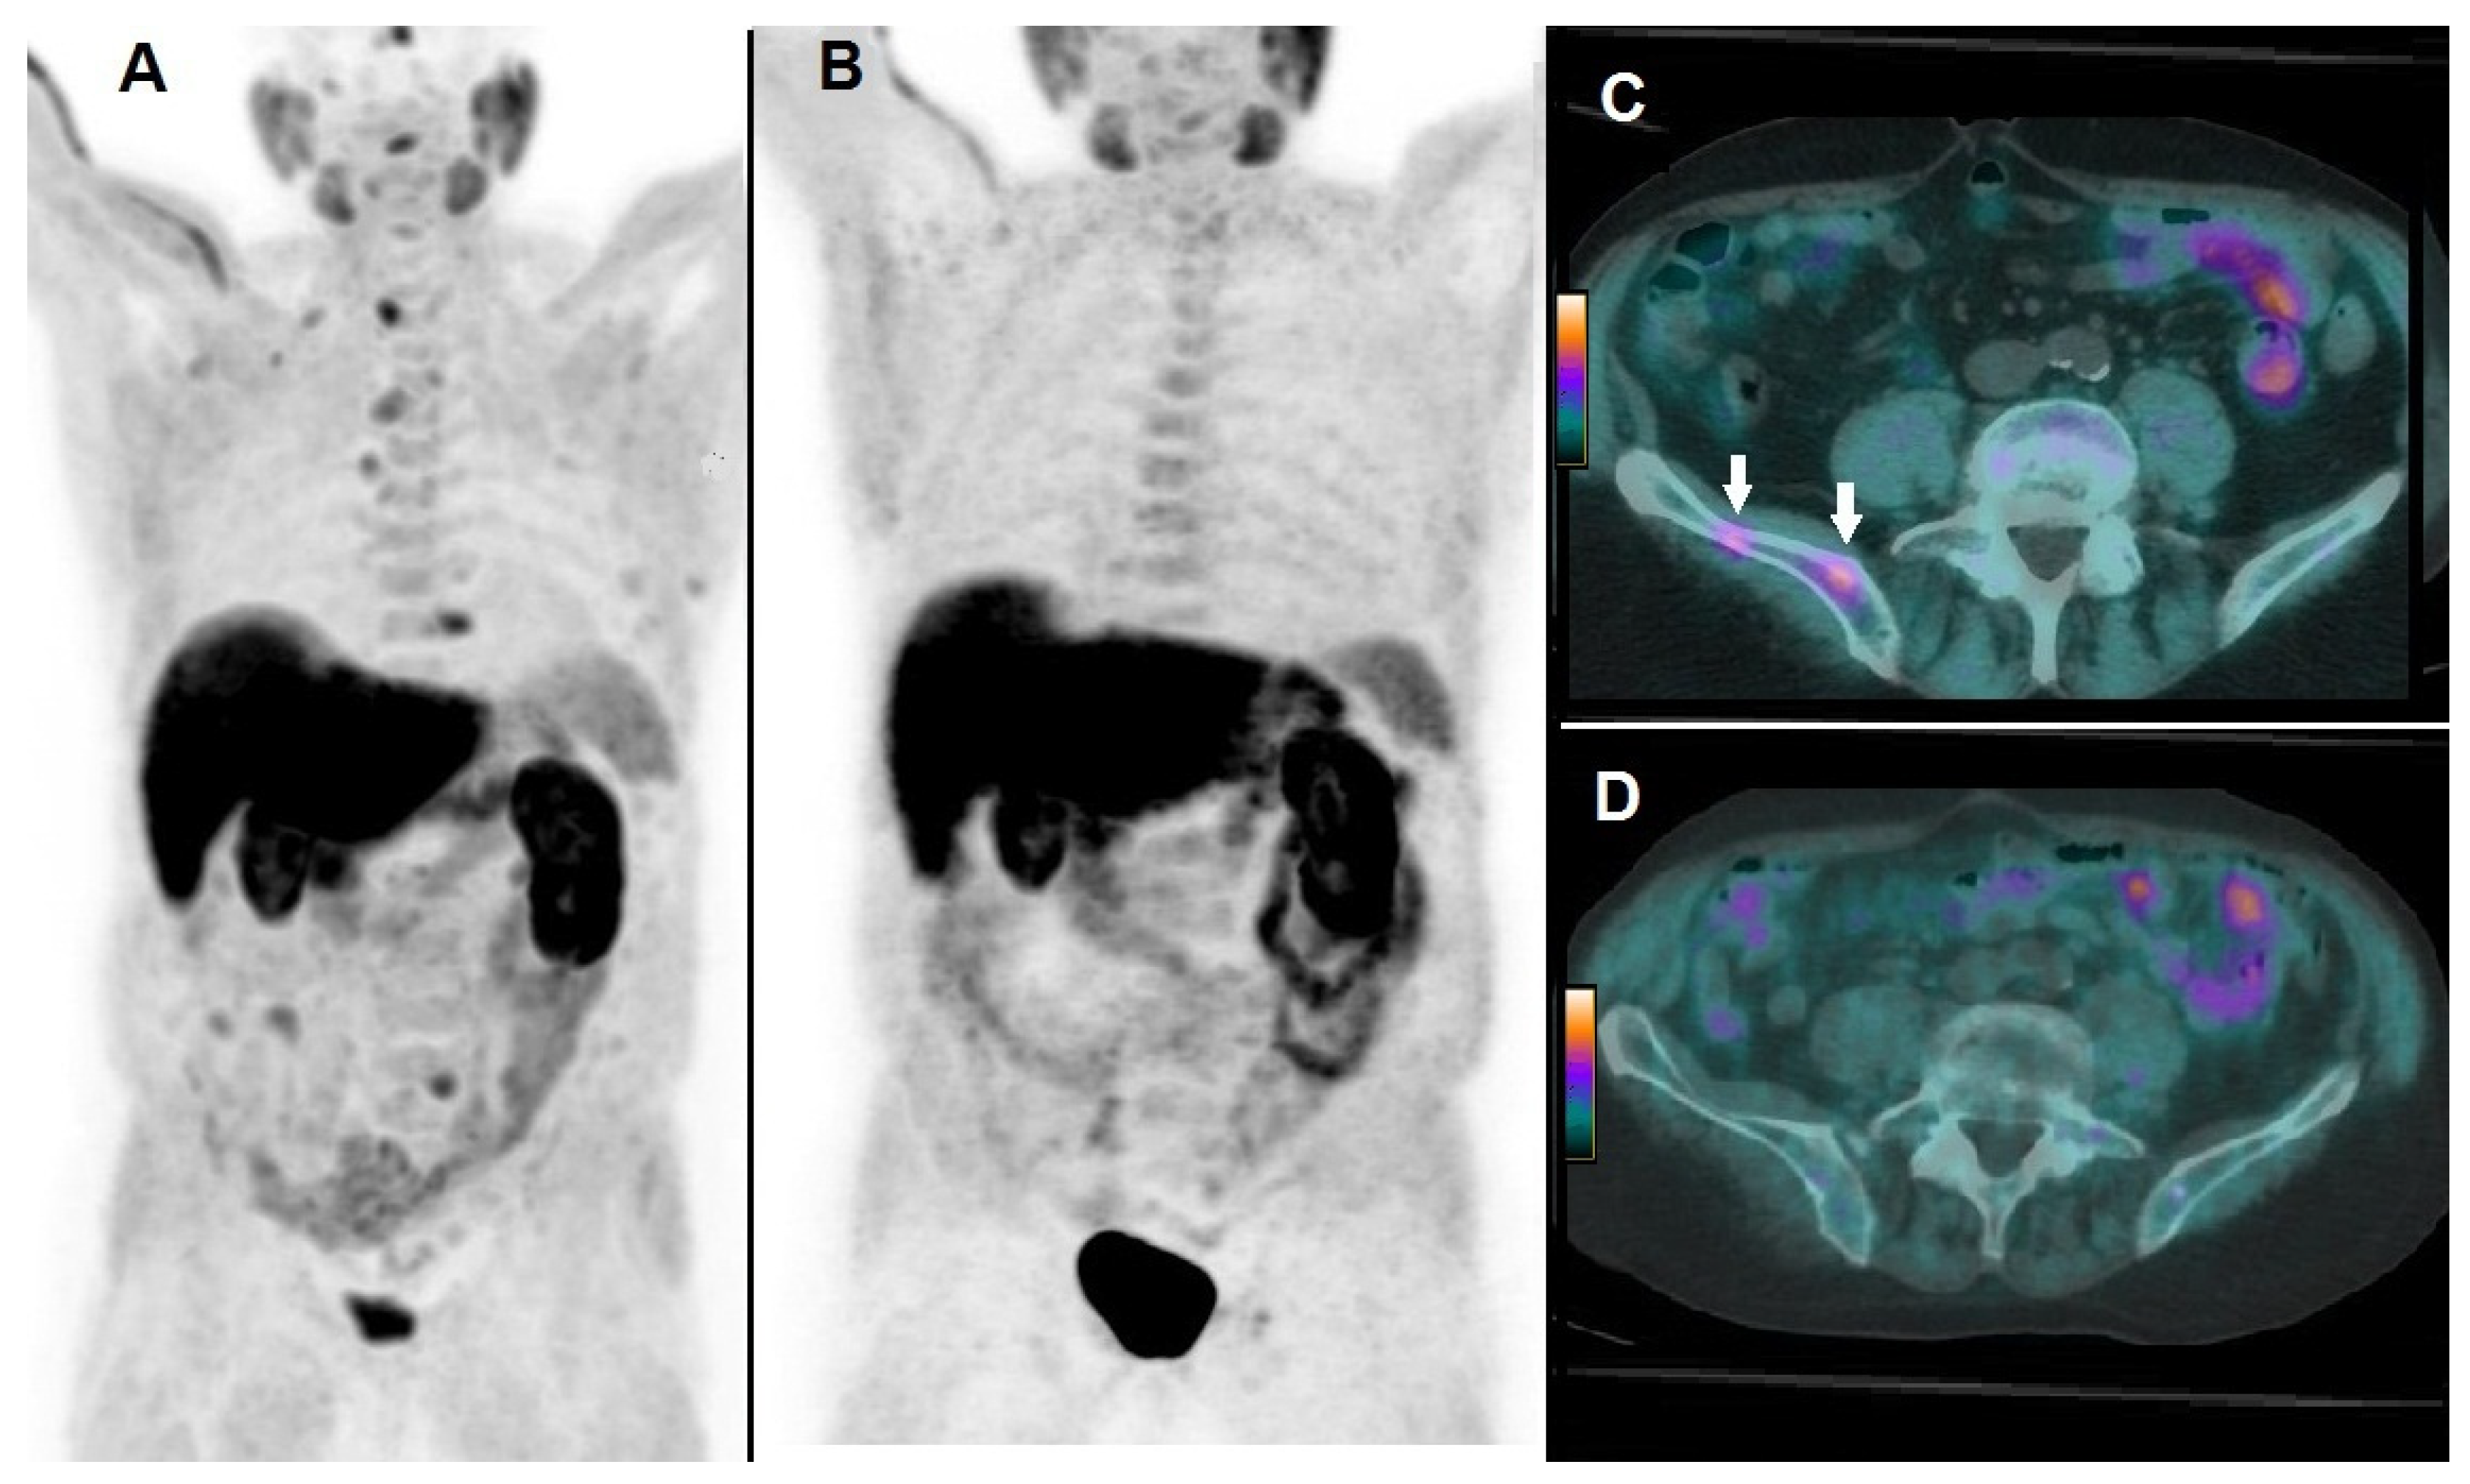

By Kaplan–Meier analysis, responders presented a significantly longer survival than non-responders (i.e., median OS = 19 months, 95% CI 15–27, vs. 8 months, 95% CI 7–13, p < 0.05), as shown by Figure 3. Emblematic examples of 18F-choline PET/CT findings in a patient with more favorable prognostic factors and clinical outcome are depicted in Figure 4, while Figure 5 describes a subject with poor prognostic factors and outcome.

Figure 4. A 74-year-old patient affected by mCRPC, previously treated with androgen deprivation therapy, subsequently submitted to 223Ra-therapy. At baseline, 18F-choline PET/CT demonstrated multiple sites of tracer uptake in bones, as evident in Whole Body (A) and the following parameters were registered: PSA = 17 ng/mL; number of lesions = 18; TLA = 235.3 g. 18F-choline PET/CT acquired after 6 cycles of 223Ra-therapy demonstrated complete metabolic response as depicted by Whole Body (B). 18F-choline PET/CT fused axial images of the pelvis acquired at baseline showed hypermetabolic lesions in the right iliac bone (C, white arrows), while post-treatment axial slices did not show any pathological sites of tracer uptake (D). Post-treatment PSA was 3 ng/mL, OS resulted in 27 months.